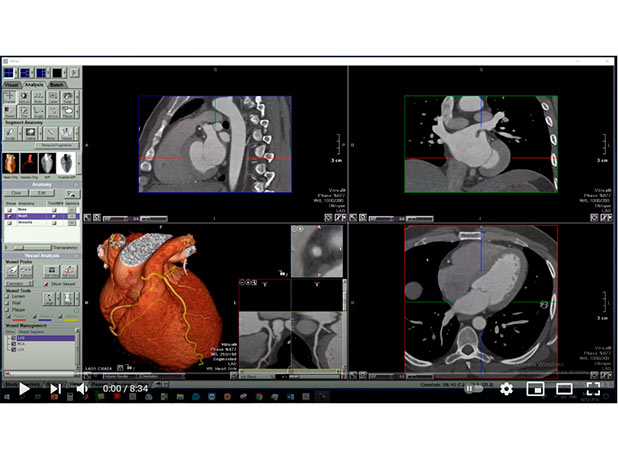

Cardiac axes

Mohamed Gibreel , FEBR (Fellowship of Egyptian Board of Radiology ) Cardiac imaging consultant at Aswan heart center -Magdi Yacoub Foundation , Egypt